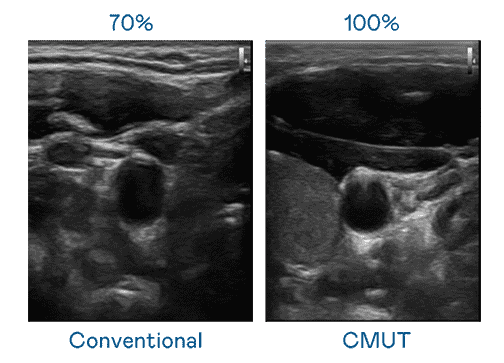

CMUT 技术是一种用电容式微机电元件来产生超音波讯号的技术。。与传统 PZT 压电式技术相比,,,,CMUT 频宽增加 30%,,,,更宽频的超音波讯号让影像解析度大幅提升,,,是实现高影像品质医疗超音波扫描、、、促进精准医疗发展的关键技术。。

大频宽带来超清晰影像

超音波影像的解析度高低,,,首先取决于探头能发出的讯号频宽。。。。人生就是博 CMUT 可提供高清晰的超音波讯号,,,,提供高频宽、、高灵敏度、、、影像纹理细节更高的超音波影像,,,,协助医护人员缩短影像判读时间及利用精准的医疗影像进行诊断。。。。